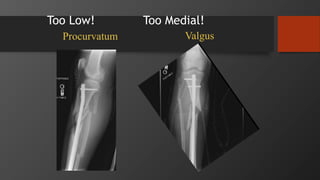

Too Low! Too Medial!

Procurvatum Valgus

Non-Operative Treatment Indications

•Stable fracture pattern

• < 5° varus/valgus

• < 10° pro/recurvatum

• < 1 cm shortening

• Coronal Angulation > 5°

• Sagittal Angulation > 10°

• Rotation > 5°

• Shortening > 1cm